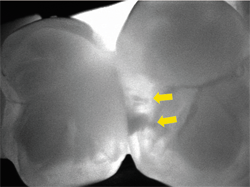

Another recent patient gave me an opportunity to use the CariVu in a new and innovative way. The patient complained that food was getting trapped under her new crown. While the contact looked acceptable on an X-ray (Fig. 16) and visually, because of the way it shows the shape and size of a tooth so well, the CariVu image showed the contact between two crowned teeth (which show as dark on a CariVu image) was just at one point instead of the necessary broad and flush contact (Fig. 17) that would prevent the food from being trapped under the gold and porcelain-fused-to-metal crowns. Flossing indicated resistance only on a small portion of the tooth. It was a great application of this technology for patient education so she could immediately understand her problem. We sent the CariVu images as additional documentation for predetermination to the insurance company to see if a new crown can be covered.

Fig. 16 Fig. 17